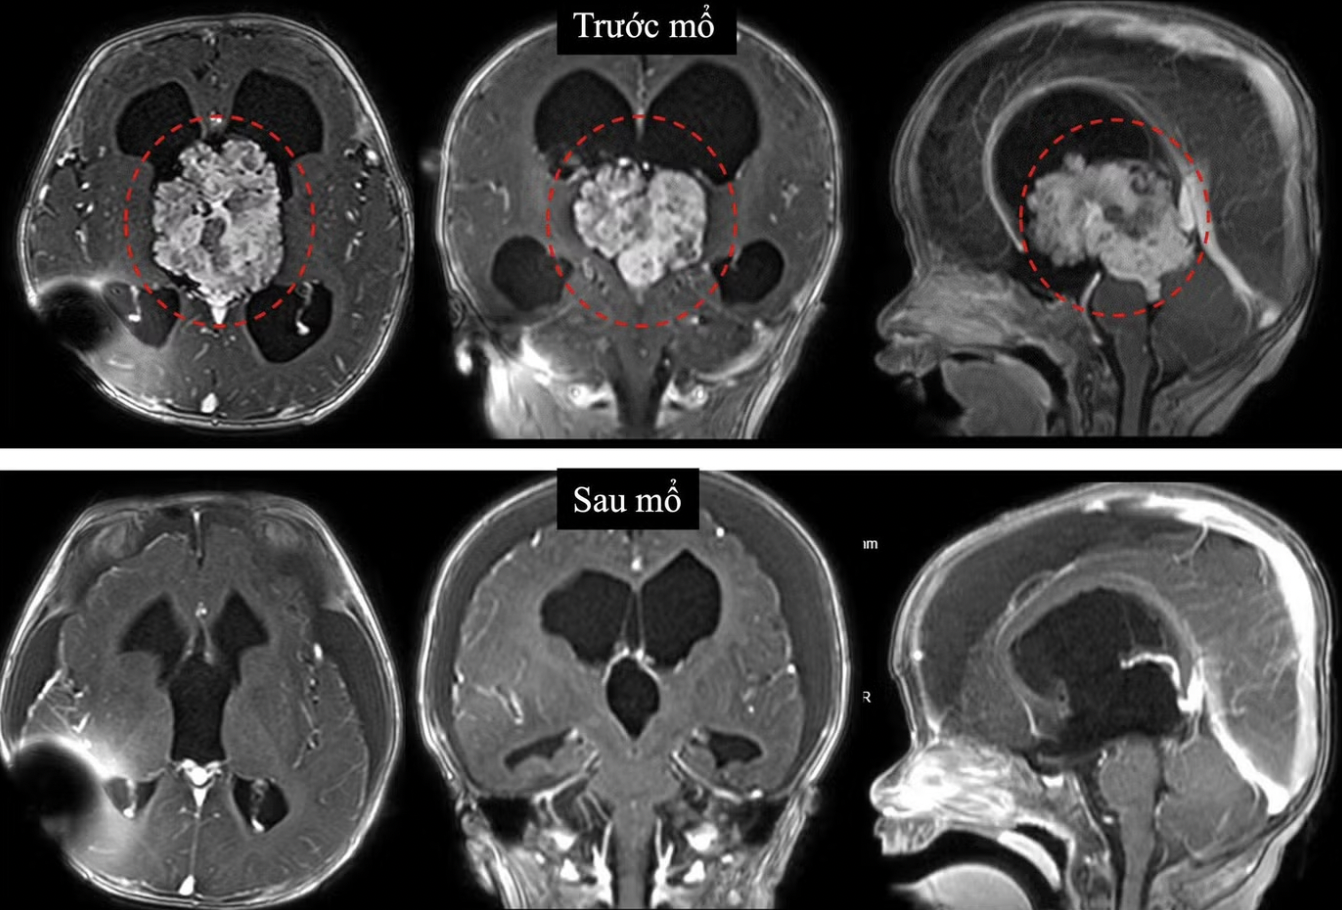

Qua thăm khám, bác sĩ ghi nhận vòng đầu của bé lớn hơn bình thường, thóp căng phồng. Siêu âm qua thóp phát hiện có khối u nằm trong não, gây chèn ép làm não bị giãn. Đây là tình trạng bệnh thường gọi là não úng thủy. Kết quả chụp cộng hưởng từ sau đó xác định khối u nằm ở não thất III, một “khoang” nằm sâu gần trung tâm não, nơi chứa dịch não tủy.

Theo phân tích của BS Huy, vị trí này đặc biệt nguy hiểm vì xung quanh là nhiều cấu trúc thần kinh và mạch máu quan trọng. Việc can thiệp phẫu thuật vì thế luôn tiềm ẩn rủi ro cao, nhất là với bệnh nhi còn quá nhỏ. Kết quả xét nghiệm mô bệnh học cho thấy đây là u đám rối mạch mạc không điển hình độ 2, một dạng u hiếm gặp của hệ thần kinh trung ương.

Ca mổ kéo dài suốt 6 giờ, ê kíp bác sĩ đã đối mặt với thử thách lớn khi khối u có kích thước tới 6cm, nằm sâu trong não và có nhiều mạch máu nuôi. Với trẻ nhỏ, nguy cơ mất máu và biến chứng trong mổ càng cao. Ê kíp phải phối hợp chặt chẽ giữa nhiều chuyên khoa, từ phẫu thuật, gây mê đến hồi sức. Nỗ lực của các bác sĩ đã bóc tách thành công khối u cho trẻ, sau phẫu thuật, sức khỏe bệnh nhi đang phục hồi khả quan.